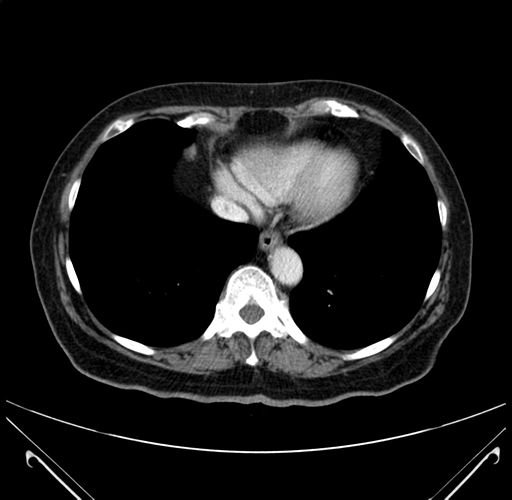

Pre-Chemo: Axial Venous

Axial Venous